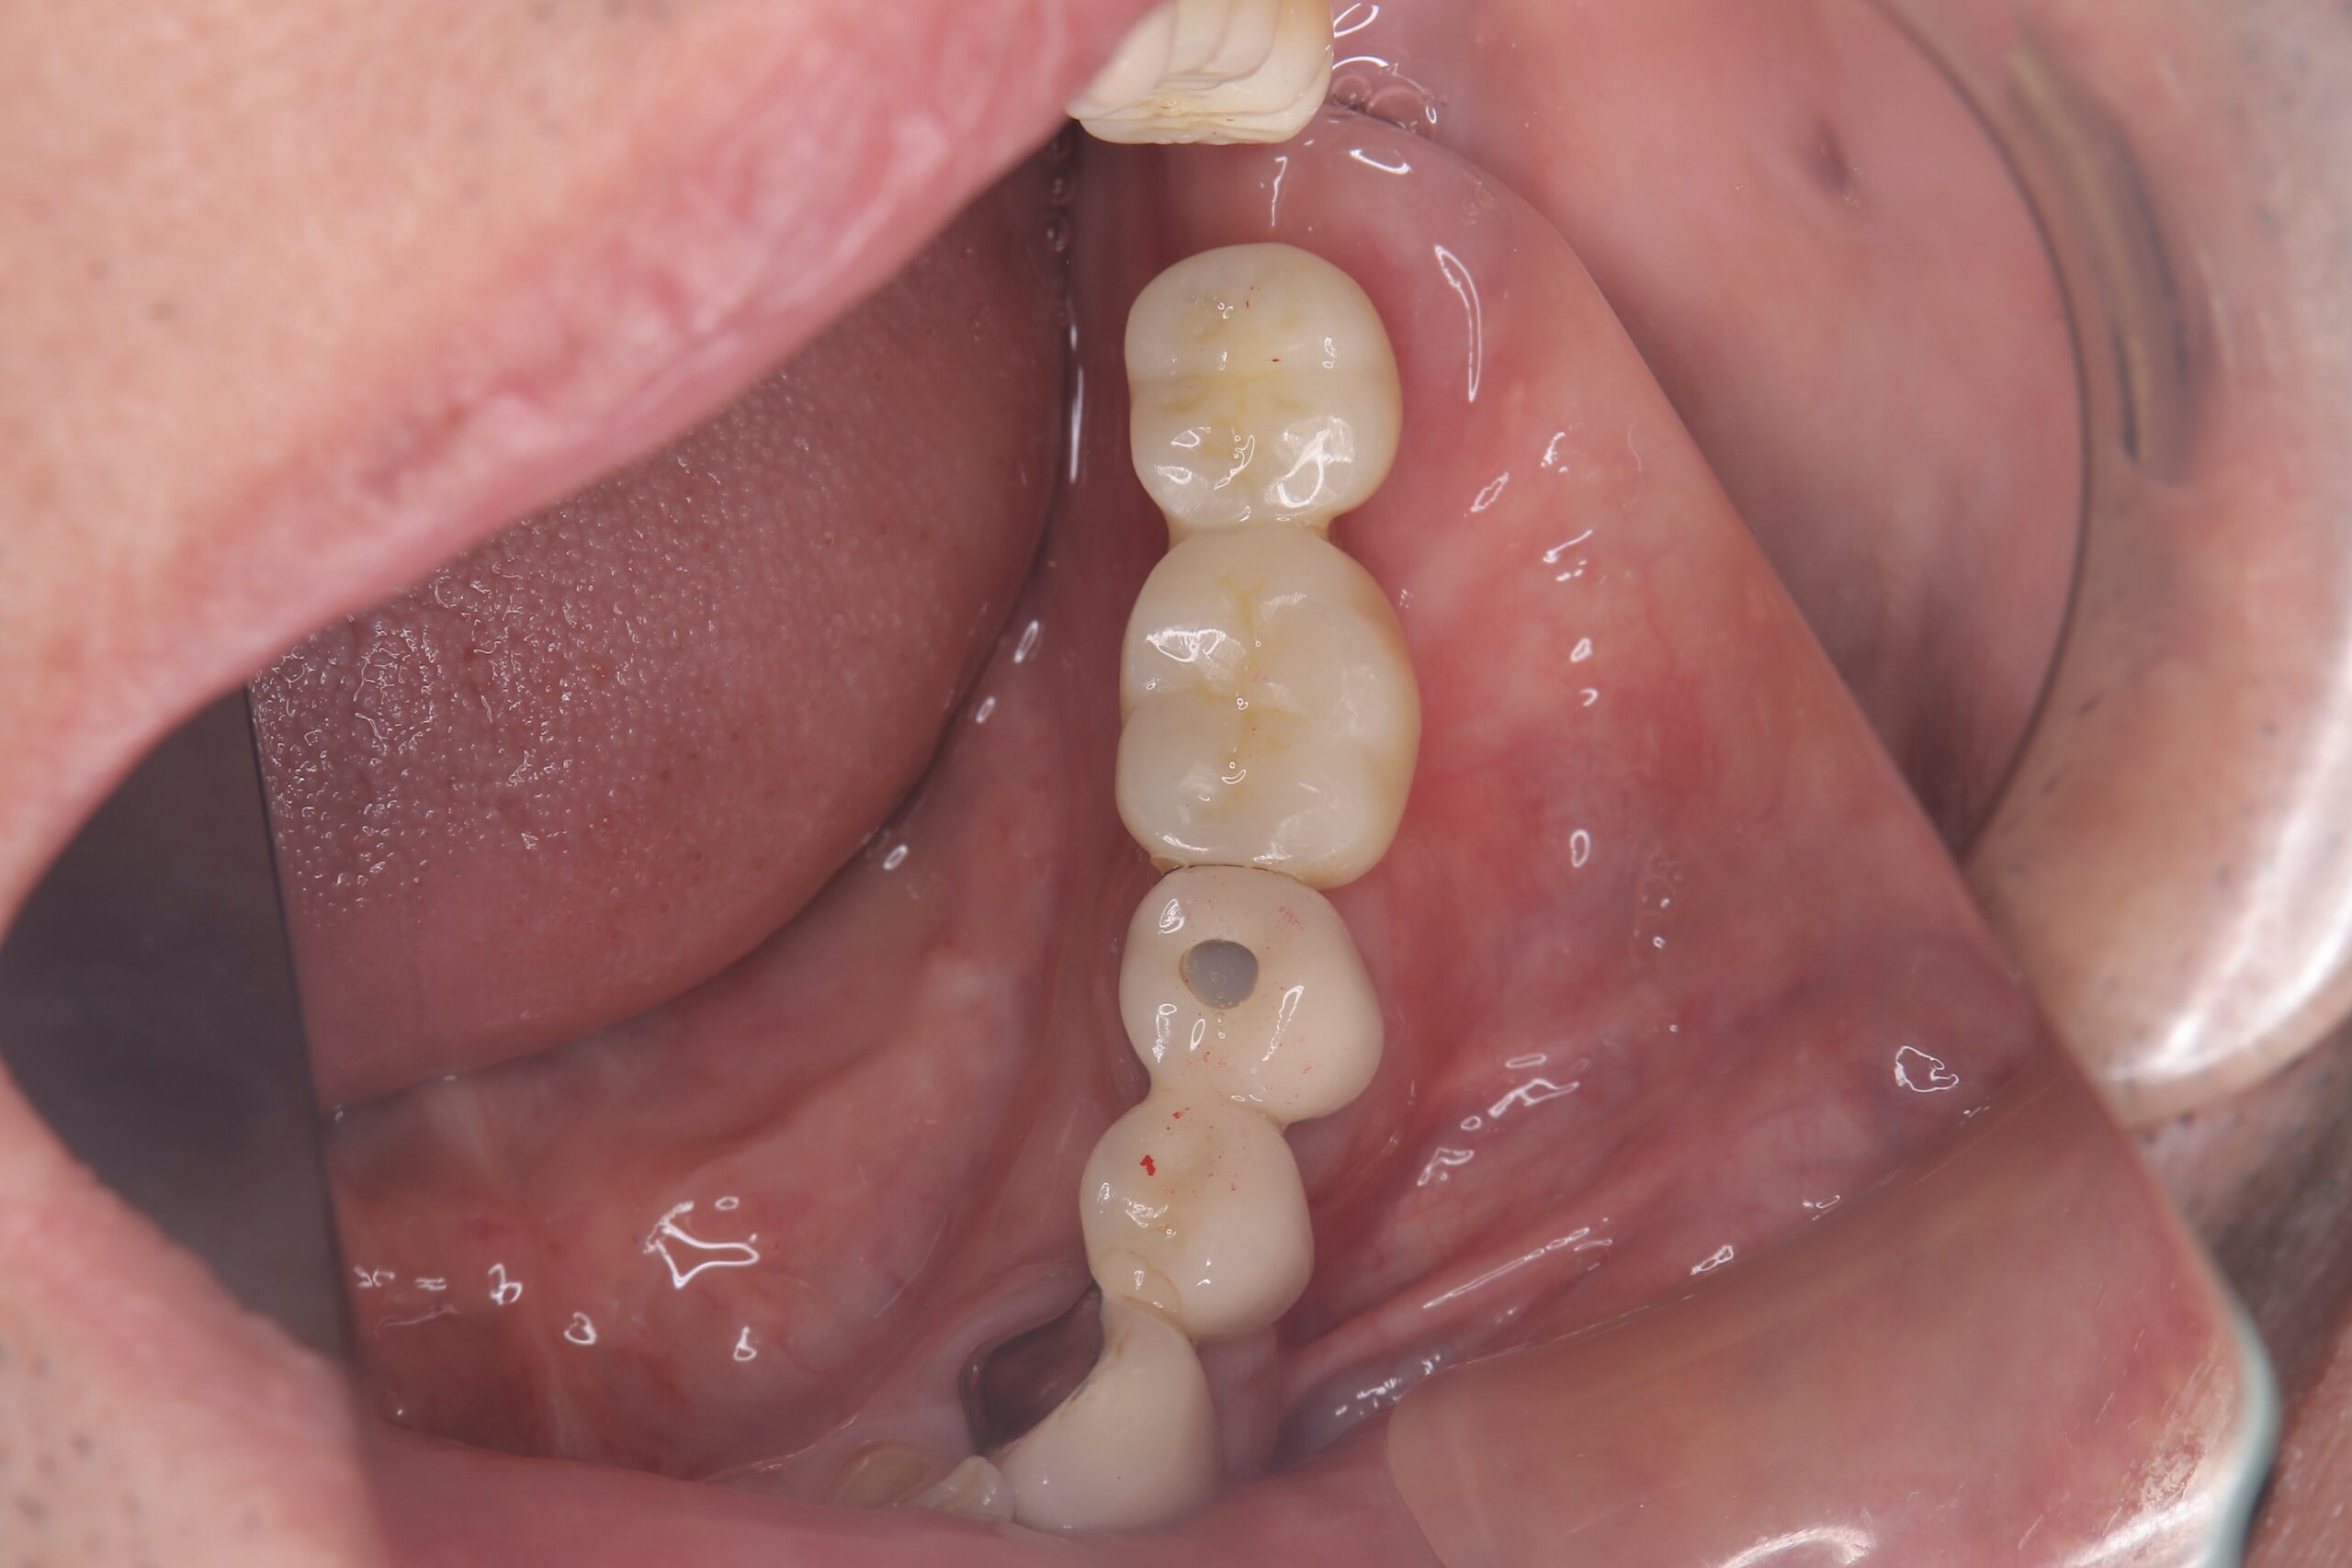

ジルコニア修復